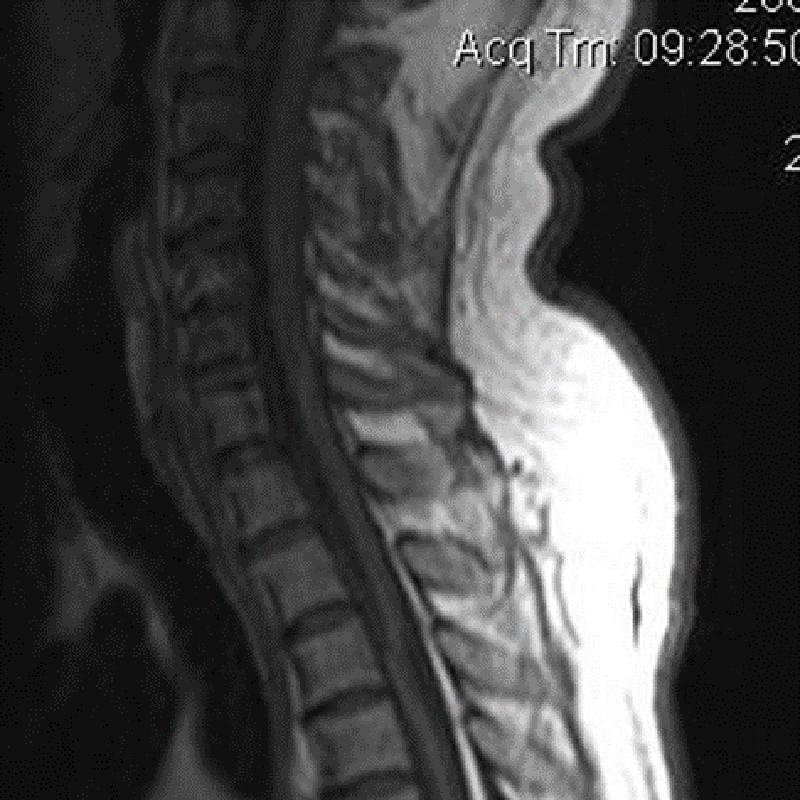

Đại cương Do những cấu trúc xung quanh của đĩa đệm cũng bị ảnh hưởng nên thuật ngữ bệnh lý thoái hóa cột sống(degenerative spine disease) thích hợp hơn thuật ngữ bệnh lý thoái hóa đĩa đệm (disc degenerative disease). Spondylosis là một thuật ngữ không đặc hiệu, nó có thể bao gồm cả bệnh lý thoái hóa cột sống. Bệnh lý thoái hóa cột sống là một quá trình […]